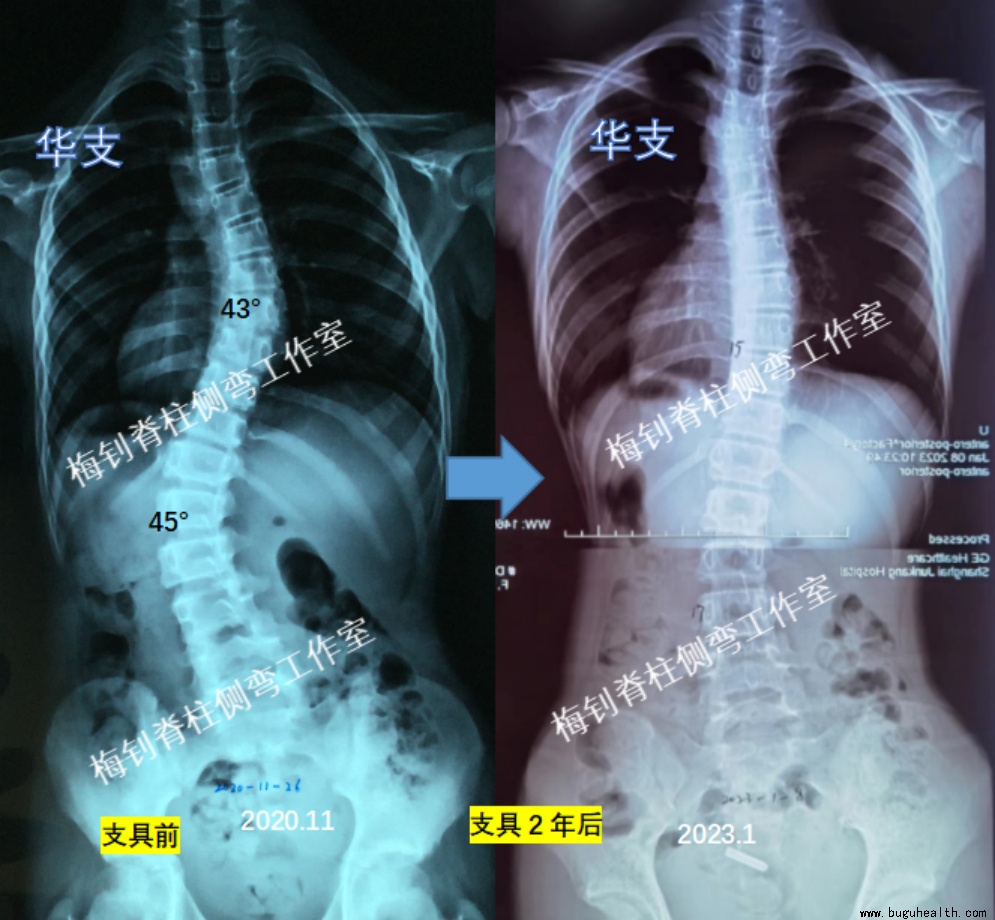

案例4

女孩,2018年10月发现侧弯,后逐渐发展,至2020年11月,胸椎弯曲达43度,腰椎弯曲45度。在当地制作支具,发现无效,及时更换我工作室支具,并因足部外翻而定制鞋垫。当时10周岁。穿戴支具后,由于压力较大,皮肤曾磨破,但孩子一直坚持穿戴,保证每天22小时以上。

2023年1月,孩子穿戴支具2年,脱支具24小时以上拍片,弯曲分别由43度和45度降低为15度和17度。期间,孩子身高增长14cm,体重增加12kg。孩子的坚持,终换来脊柱的好转,远离了手术线。